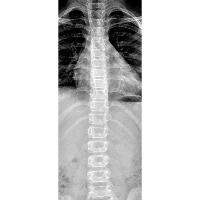

MODELO DE VISIÓN ARTIFICIAL SCONET - CLASIFICADOR AUTOMATIZADO DE PUNTOS CLAVE EN COLUMNA PARA EVALUACIÓN DE ESCOLIOSIS (Scoliosis).

SCONET ARTIFICIAL VISION MODEL - AUTOMATED KEY POINT CLASSIFIER IN THE SPINE FOR SCOLIOSIS EVALUATION.

En este proyecto se presenta el desarrollo de un modelo de visión artificial basado en una arquitectura de red YOLO-NAS-POSE aplicado en el procesamiento de imágenes médicas de tipo Rayos-X digital. Con el objetivo de automatizar la clasificación del patrón de curvatura espinal Lenke y la localización de puntos clave necesarios para el cálculo de gravedad de curvatura Cobb (Cobb Angle)a fin de agilizar la evaluación de pacientes con desviaciones en columna “Escoliosis”.

In this project, the development of a computer vision model based on a YOLO-NAS-POSE network architecture is presented, aimed at processing digital X-ray medical images. The goal is to automate the classification of the Lenke spinal curvature pattern and the localization of key points necessary for calculating the Cobb (Cobb Angle) curvature severity in order to streamline the evaluation of patients with spinal deviations such as "Scoliosis".

Metadatos de Base de datos • Población de muestra: Pacientes con desviaciones de columna (Escoliosis idiopática) y pacientes sanos. Se incluyen hombres y mujeres. Rango de edad: [11 - 30] años

Tipo de imagen: • Radiografías digitales en plano anteroposterior completo

**Cada punto clave en columna fue verificado y reajustado por nuestro asesor especialista en radiología e imagen. **